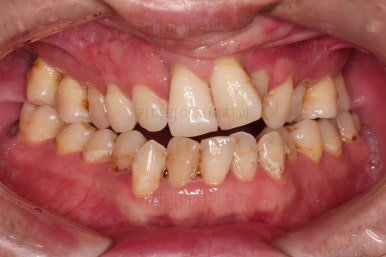

1. 초진 시 입안의 모습

부산구순구개열교정 키다리아저씨치과에 처음 내원하셨을 당시의 입안의 모습입니다.

구순구개열 환자분의 일반적인 입 안의 특징은 다음과 같습니다.

골 결손부위의 치아 결손이 빈번하다.

구개열 봉합술을 어린 나아이에 받기 때문에, 해당 부위의 상흔이 남는다.

상흔의 영향으로(피부 상처도 일반 피부 보다는 상처가 아문 부위가 더 단단하죠.) 입천장의 잇몸이 굉장히 단단하다.

그래서 가로폭의 성장이 잘 되지 못하여 악궁(치아가 배열된 U자 형태)이 협착된 경우가 많다.

공간 부족으로 치열이 매우 삐뚠 경우가 많다.

공간 부족과 악궁 형태 등으로 인해 부정교합이 함께 나타난다.

골 결손부위 근처의 치아는 뼈가 약한 경우가 많아 튼튼하지 못하고 만지면 흔들리는 경우가 많다.

이번 환자분도 이와 같은 일반적인 특징이 그대로 나타나 있었습니다.

양측성 구순구개열이었으므로 작은 앞니(대문니와 송곳니 사이)가 양쪽 다 결손이었고, 또 다른 이유로 아래 앞니도 1개 없는 상태였습니다.